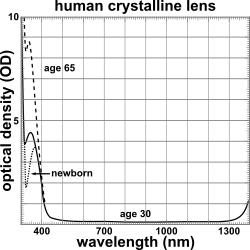

The lens blocks most ultraviolet light in the wavelength range of 300–400 nm; shorter wavelengths are blocked by the cornea. High intensity ultraviolet light can harm the retina, and artificial intraocular lenses are therefore manufactured to also block ultraviolet light.[14] People lacking a lens (a condition known as aphakia) perceive ultraviolet light as whitish blue or whitish-violet.[15][16]